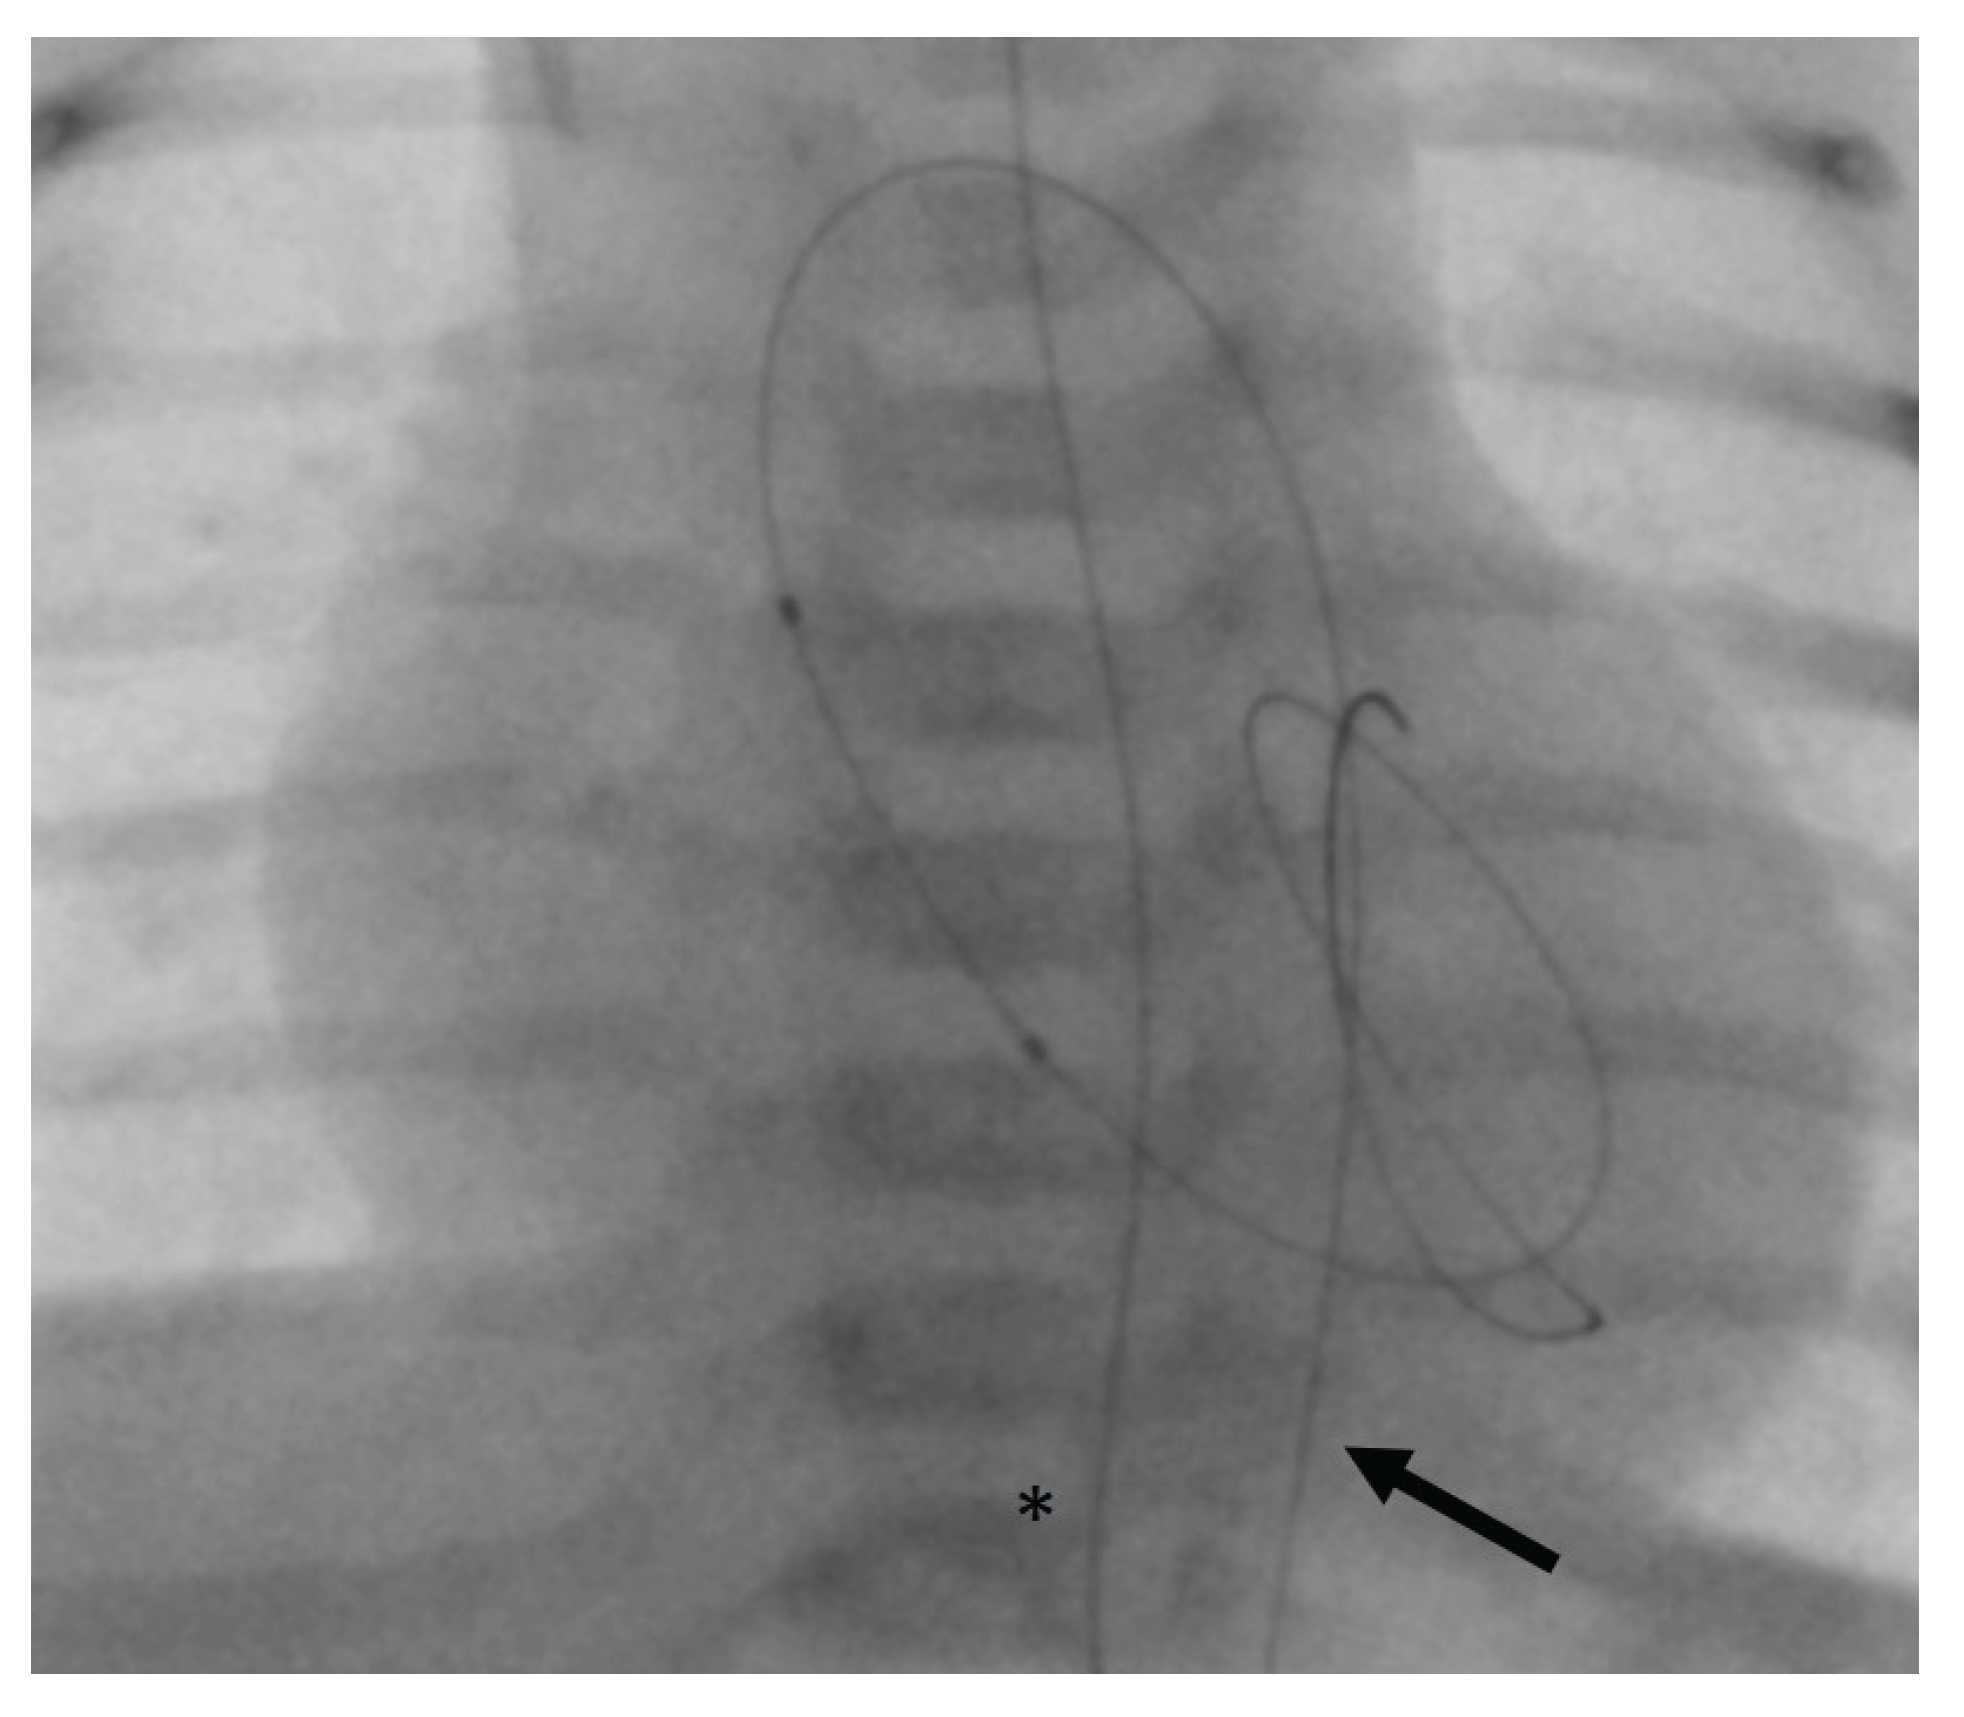

If retrograde catheterization was not feasible, a trans-venous antegrade approach was accomplished via lower vena cava, right atrium, foramen ovale, left atrium, and LV. After passing the AV into the ascending aorta, the guidewire was caught using a retrieval loop (Multi-Snare©, pfm medical mepro gmbh, Nonnweiler-Otzenhausen, Germany, 5 or 10 mm diameter) that was inserted retrogradely into the aorta (Figure 2a). Then, it is possible to pull the wire into the descending aorta and fixate it stably during the BAV (Figure 2b).

Figure 2. Angiography of balloon aortic valvulotomy (BAV) with antegrade access (posterior-anterior projection). (a) A coronary guidewire (asterisk) is positioned trans-venously up to the ascending aorta where it is snared by a trans-aortic inserted loop (arrow); (b) After catching of the guidewire (asterisk), it is attached by the snare catheter (arrow) in the descending aorta to ensure stable balloon support during BAV.